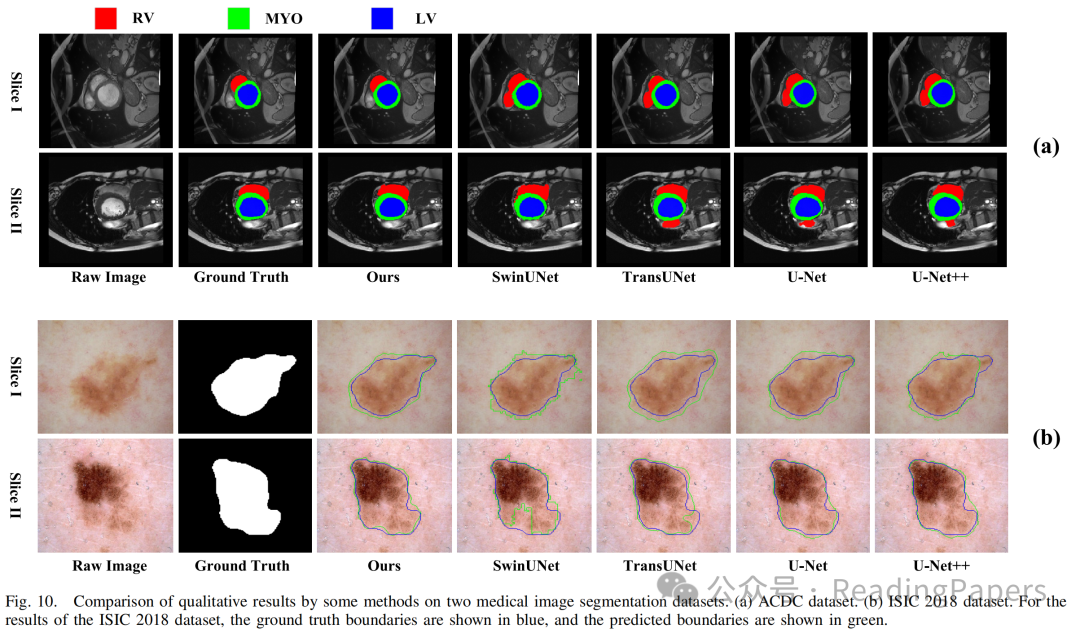

Transformer通过自注意力机制在医学图像处理中取得了显著进展,能够建模长距离语义依赖关系,但其缺乏卷积神经网络(CNN)捕捉局部空间细节的能力。本文提出了一种基于混合CNN-Transformer(MixFormer)特征提取骨干网络的新型分割网络,旨在提升医学图像分割的效果。MixFormer网络在下采样过程中无缝集成了Transformer和CNN架构的全局和局部信息。为了全面捕捉跨尺度的视角,作者引入了多尺度空间感知融合(MSAF)模块,有效实现了粗粒度与细粒度特征表示之间的交互。此外,作者还提出了混合多分支扩张注意力(MMDA)模块,用于在编码和解码阶段之间弥合语义差距,同时强调特定区域。最后,作者采用基于CNN的上采样方法来恢复低级特征,显著提高了分割精度。通过在多个主流医学图像数据集上的实验验证,MixFormer表现出卓越的性能。在Synapse数据集上,该方法达到了82.64%的平均Dice相似系数(DSC)和12.67 mm的平均Hausdorff距离(HD)。在自动心脏诊断挑战(ACDC)数据集上,DSC达到了91.01%。在国际皮肤成像协作(ISIC)2018数据集上,模型的平均交并比(mIoU)为0.841,准确率为0.958,精确率为0.910,召回率为0.934,F1得分为0.913。在Kvasir-SEG数据集上,平均Dice为0.9247,mIoU为0.8615,精确率为0.9181,召回率为0.9463。在CVC-ClinicDB数据集上,平均Dice为0.9441,mIoU为0.8922,精确率为0.9437,召回率为0.9458。这些结果表明,MixFormer在分割性能上优于大多数主流分割网络,如CNN和其他基于Transformer的结构。